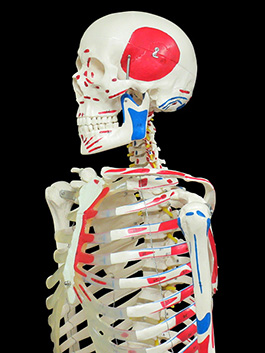

大人 可愛い 服 全身骨格(神経筋肉系)模型 引き取りのみ その他